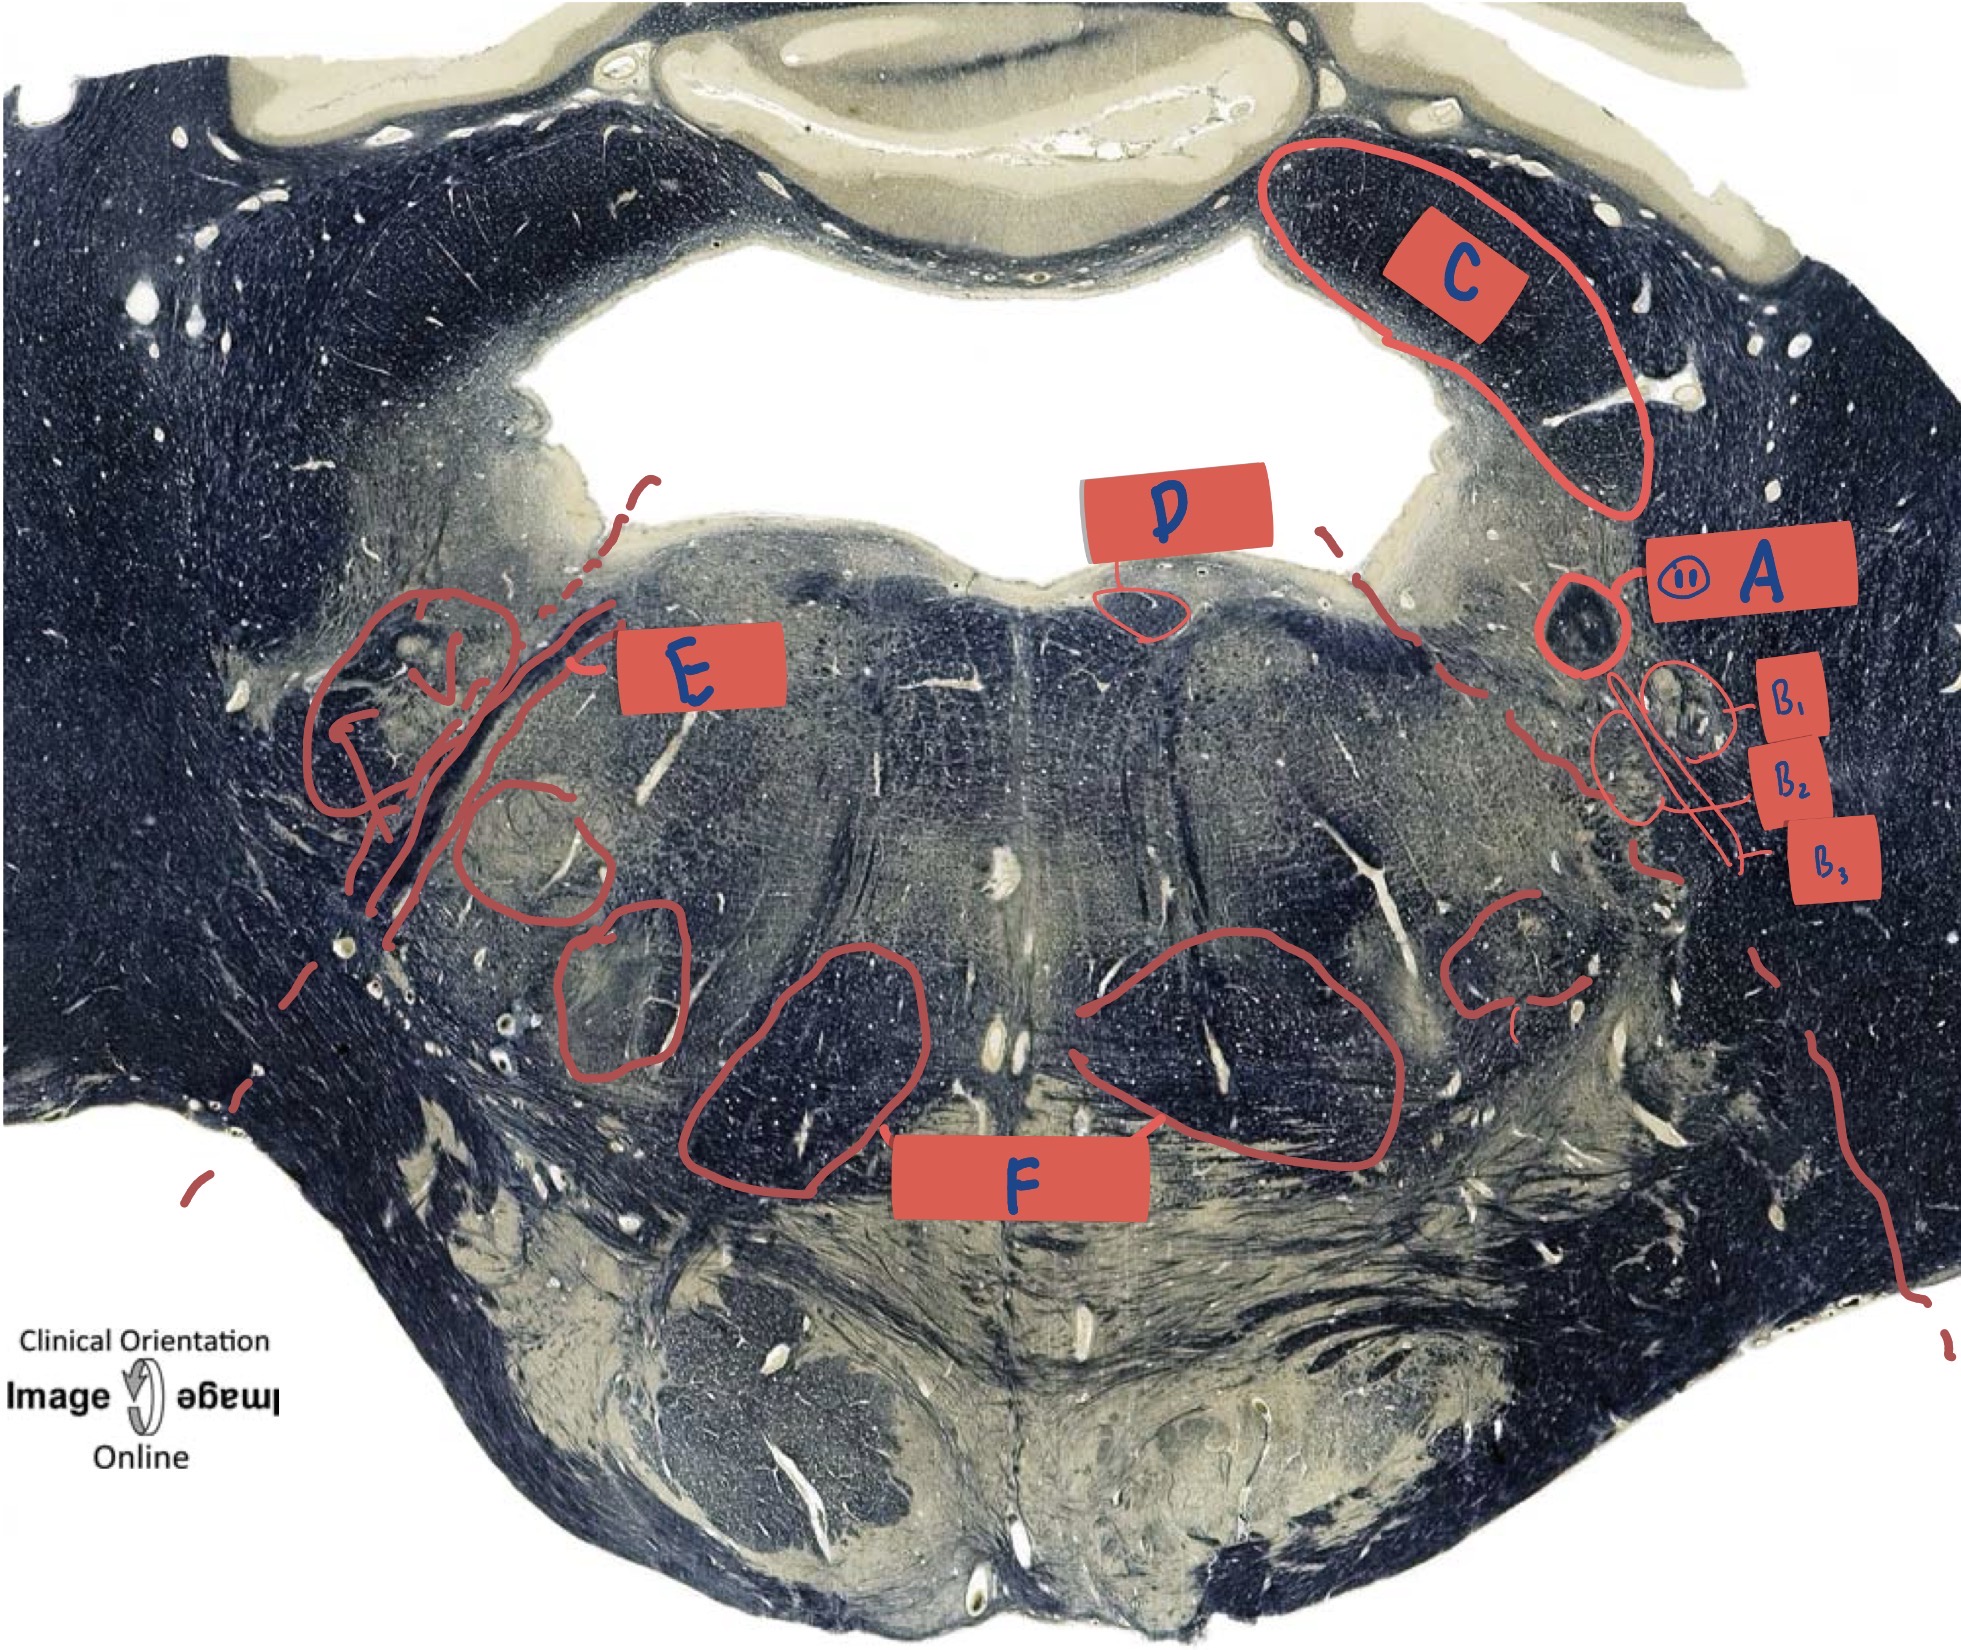

What is A?

Gracile fascicullus

What is B?

Cuneate fasciculus

What is C?

Spinal trigeminal tract

What is D?

Anterolateral System

What is E?

Pyramidal Decussation

What is F

Pyramid

What is G?

Olive

What is H?

Spinal trigeminal nucleus